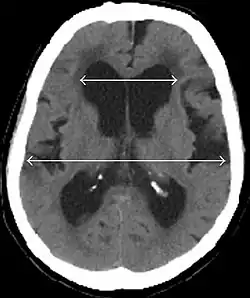

Diagnostisch sollte bei vorliegender klinischer Symptomatik ein CT oder alternativ MRT des Gehirns angefertigt werden. Eine (krankhafte[26]) Erweiterung der inneren[27][26](besonders der Vorder- und Temporalhörner[26]) und äußeren[26] (besonders der Sylvischen Fissur[26]) Liquorräume ist typisch.

Hinweise auf einen Normaldruckhydrozephalus sind:

- Evans-Index(maximaler Innendurchmesser der Frontalhörner der Seitenventrikel dividiert durch maximalen Innendurchmesser des Schädels) > 0,3[27] auf Höhe des Foramen Monroi[28] im axialen Schnitt[28], das heißt eine Erweiterung der Seitenventrikel